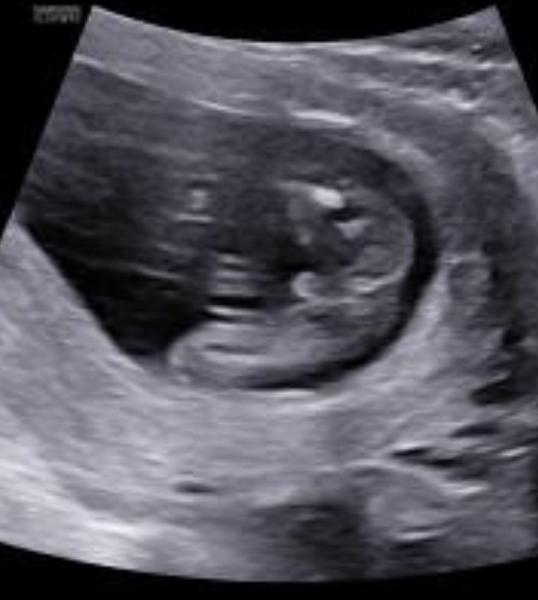

Je to holka nebo kluk? Jak rozeznat z fotky?

Ahoj, chtěla bych poprosit, myslíte si, ze na přiložené fotce je holka, nebo kluk, vidim pindika i kávové zrno 🙂 Díky moc

Pindík, vypadá to dost celistvě, syn měl to samé. Kávová zrna jsou o něco větší.

@zeb007 zapomněla jsem uvést, ze fotka je z 16 tt